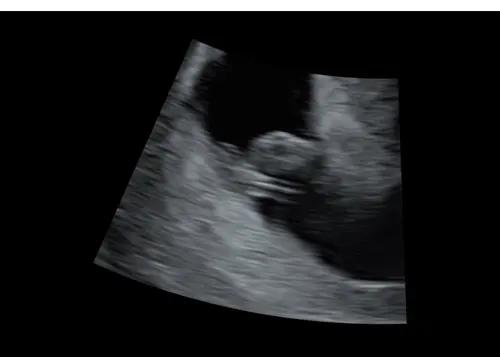

Hierbij nog eentje, dit was van mn inwendige echo. Op ongeveer iets meer dan 6 weken. 馃榿

Hierbij nog eentje, dit was van mn inwendige echo. Op ongeveer iets meer da ...

baby boy馃挋